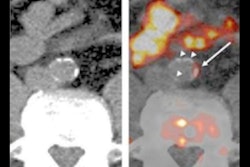

Gallium-68 (Ga-68) pentixafor binds to the CXCR4 receptor on inflammatory cells present in atherosclerotic plaques, which makes it possible to find and treat atherosclerosis in its early stages (JNM, March 2017, Vol. 58:3, pp. 499-506).

Ga-68 pentixafor's ability to bind specifically to inflammatory cells in atherosclerotic plaques was validated in animal models and human subjects. Images showed inflammation in plaques in the abdominal aorta and right carotid artery of atherosclerotic rabbits. The researchers also confirmed that the radiotracer detected atherosclerotic plaques located in the carotid arteries of a small number of human patients.